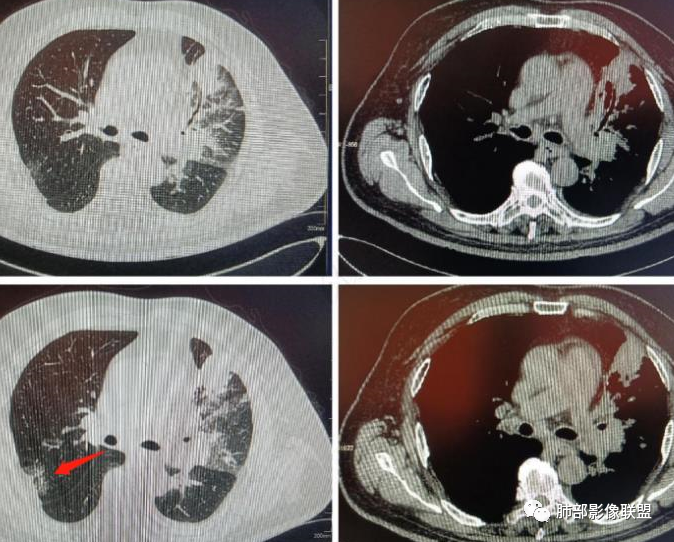

一、简要病史:老年男性,咳嗽咳痰1月,少许白痰、易咳出,稍感胸闷,无发热等其他不适。既往糖尿病及右下肢深静脉血栓病史,无吸烟史。二、实验室检查:CRP稍高,白细胞正常,无其他有价值的实验室检查提供。

三、影像表现:左肺上叶多发片状高密度影,散在,边缘模糊,支气管壁稍增厚,中轴间质、小叶间隔增厚、有结节感,左肺上叶前段病灶可见胸膜增厚,部分小支气管不能分辨;右肺上叶后段混合磨玻璃结节,边界清,邻近胸膜凹陷;纵膈淋巴结肿大;心包增厚;左侧少量胸水。此外,扫及右侧胸腔内甲状腺肿;左侧肩胛骨旁肌群内脂肪瘤。

四、综合分析:老年男性,以咳嗽咳痰为主要临床表现,无发热,白细胞正常,影像表现为左肺上叶片影,前段结节影、胸膜增厚、部分小支气管不能分辨。左肺上叶中轴间质增厚、小叶间隔增厚、结节感,肺门纵隔见肿大淋巴结,尽管肺部病病灶边缘特征不典型,但高度疑及癌性淋巴管炎这一“次生灾害”却具有相当重要提示意义,而肺癌中最常伴癌淋的就包括腺癌。右肺上叶后段混合磨玻璃结节,边界清楚,张力明显,具有一定特征性,高度指向浸润性腺癌。这对于左肺病灶具有一定程度“助攻”效应。总体而言,本例左肺病灶的诊断关键点在于判断出癌性淋巴管炎。癌性淋巴管炎的结节在外围间质多见,小叶间隔可呈串珠状、结节状增厚,由于出血及水肿,小叶间隔增厚较明显,或呈不规则增厚。有的肺小叶呈多角状阵列。常合并胸水。

病理结果:腺癌

因为组织少,没有做免疫组化。上靶向药了,选的埃克替尼。